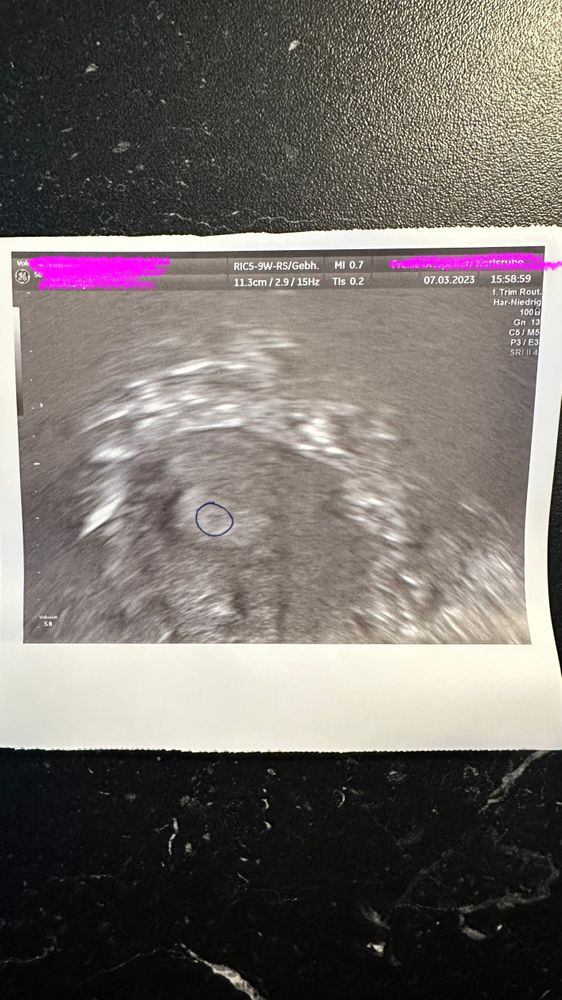

Узи не видно ни чего Хгч 405.0 , по месячным 5 недель беременности 9 дней задержка

Здравствуйте девочки, 9 день задержки тесты с яркими полосками по Узи не чего нет , началась мазня , не чего не болит . Уровень хгч 405.0 сказали что есть три варианта . 1 замер плод .2 очень маленький срок . 3 внематочная . У кого так было ? Не знаю что и думать прием через неделю.

Привет всем , за сутки Хгч повысился на 135 в итоге 5 недель 4 дня 540 на узи увидели маленькую точку как для меня там вообще не чего не но врачам виднее , спали это и есть беременность только очень маленький срок .